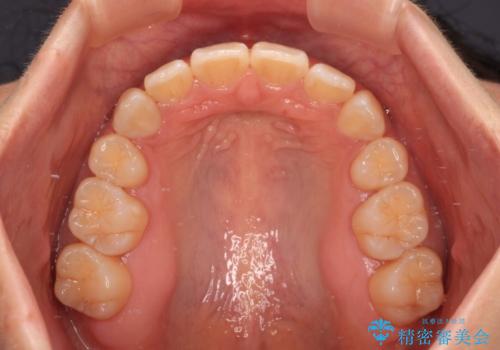

- 前歯の出っ歯と口元の閉じにくさを気にして来院された患者様です。

口元を積極的に引っ込めるために、上下左右の小臼歯4本を抜歯し、目立たないワイヤー装置にて矯正治療を行うこととしました。

上下前歯の歯軸の角度が大きく改善され、お口を閉じたときに顎先に認められた梅干し様の皺も改善されました。